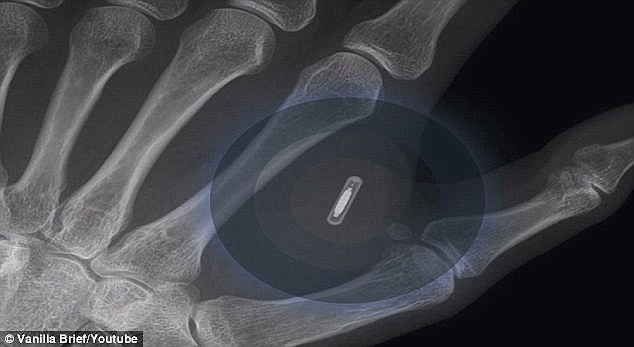

Công nghệ này được xem là trào lưu của tương lai. Các con chip điện tử có kích thước bằng một hạt gạo được cấy qua một ống tiêm vào phía sau da bàn tay.

Các micro chip chỉ nhỏ như hạt gạo sẽ được cấy vào giữa ngón cái và ngón trỏ

Những con chip với kích cỡ chỉ bằng hạt gạo (Ảnh: BioHax International)